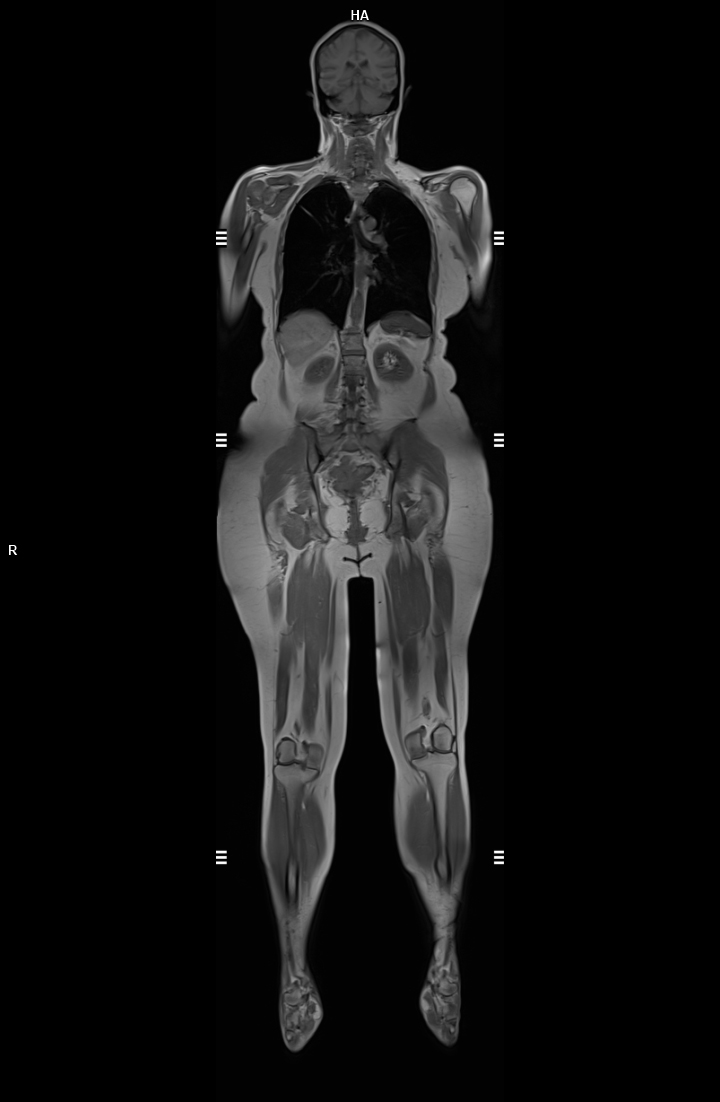

• 3 TESLA MR ÇEKİM GÖRÜNTÜLERİ

3 Tesla MR Çekim Görüntüleri

• 3 Tesla MR Çekim Görüntüleri